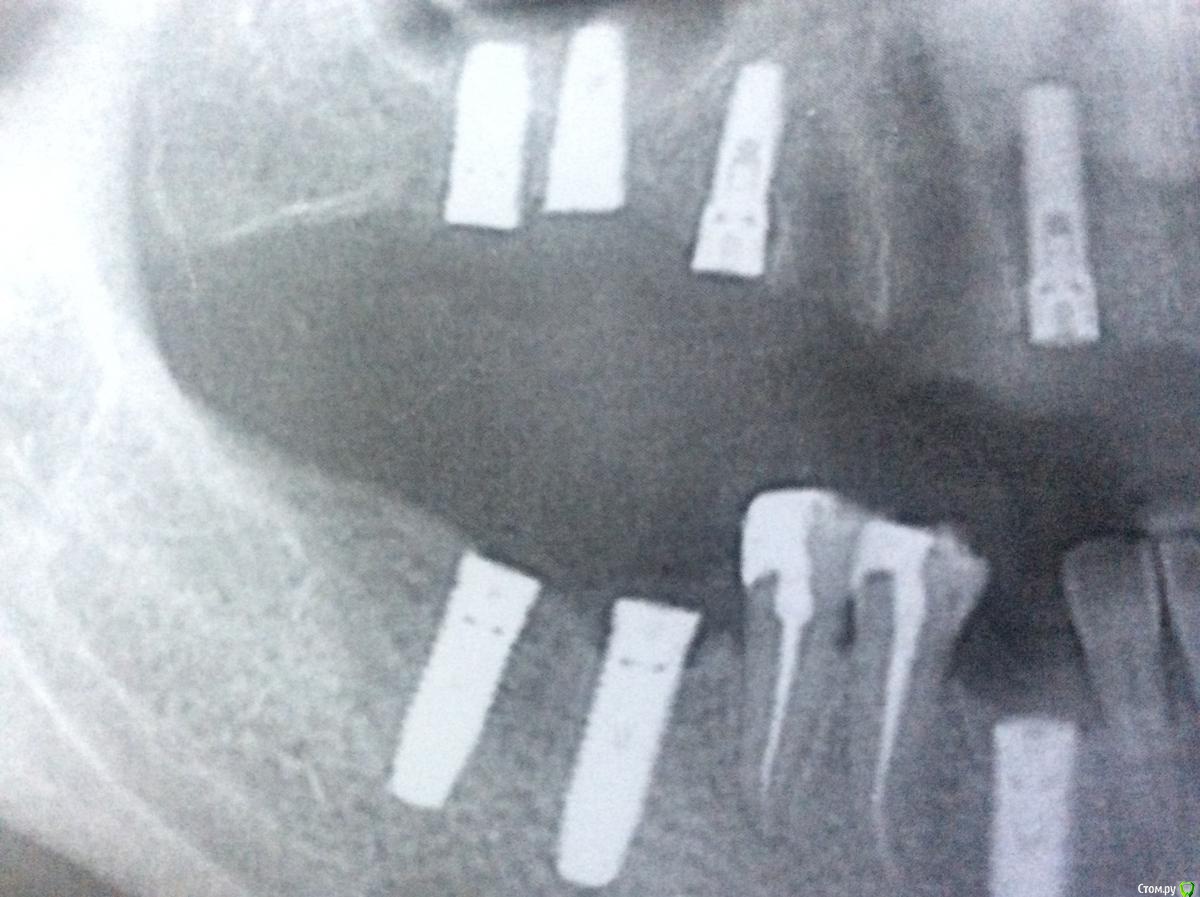

МарияЯ Опубликовано 5 августа, 2018 Автор Поделиться Опубликовано 5 августа, 2018 На руках только распечатанный снимок. Вот максимально приближенное фото установленных имплантатов Ссылка на комментарий

red_butler Опубликовано 6 августа, 2018 Поделиться Опубликовано 6 августа, 2018 Можно ли доверять определению системы имплантатов по ОПТГ? это как викторина 81 просмотр и ни одного ответа качество снимка не позволяет дать ответ Ссылка на комментарий

red_butler Опубликовано 6 августа, 2018 Поделиться Опубликовано 6 августа, 2018 Я правильно Вас поняла, что ответ возможен, но только при хорошем качестве снимка?по рентгену можно попытаться угадать производителя и марку Ссылка на комментарий

Bier Опубликовано 7 августа, 2018 Поделиться Опубликовано 7 августа, 2018 Мария, некоторые имплантаты имеют прямо характерную узнаваемую форму и легко узнаются на снимках. А некоторые очень похожи между собой и тогда получается гадание на кофейной гуще. Я не работал ни НИКО ни Семадосом по этому ответ дать сложно. Но как правило во рту у пациента стоит именно то, что записано в карточке. Ссылка на комментарий